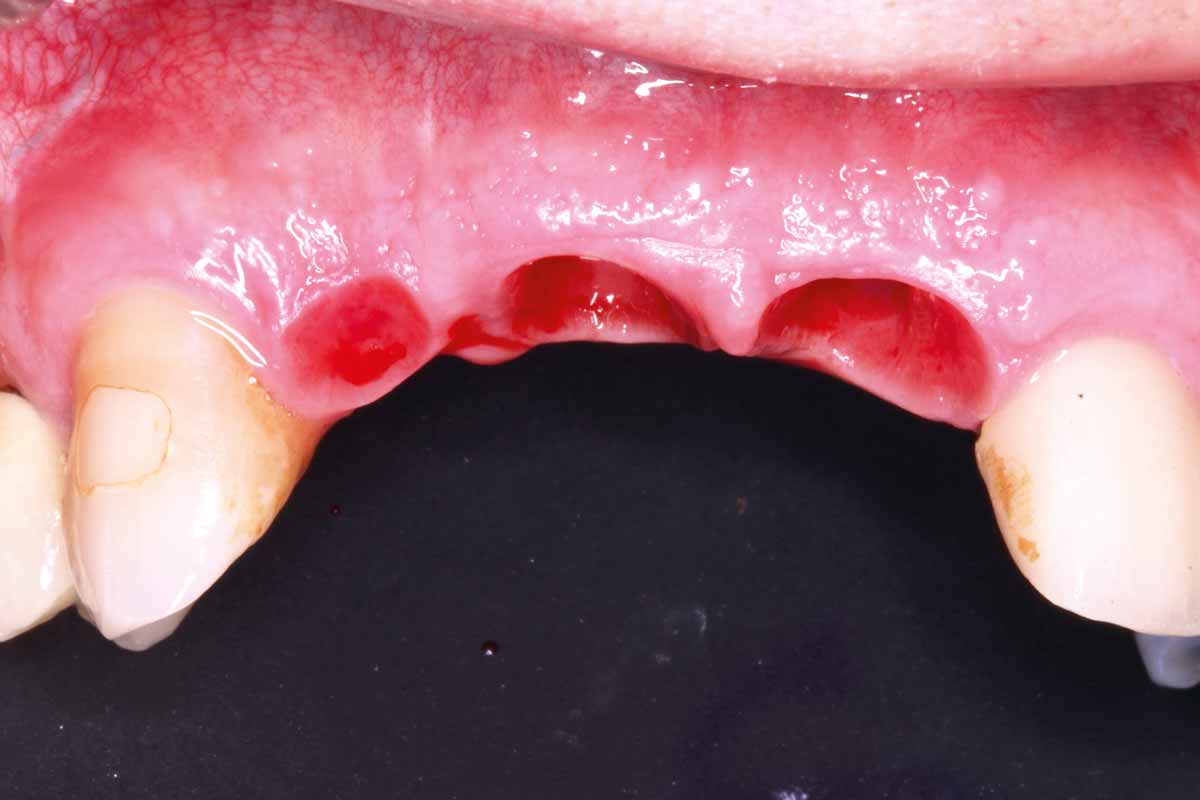

4/27 - Bone defect after extraction: occlusal view

GBR and soft tissue augmentation with cerabone® and mucoderm® - H. Maghaireh & V. Ivancheva